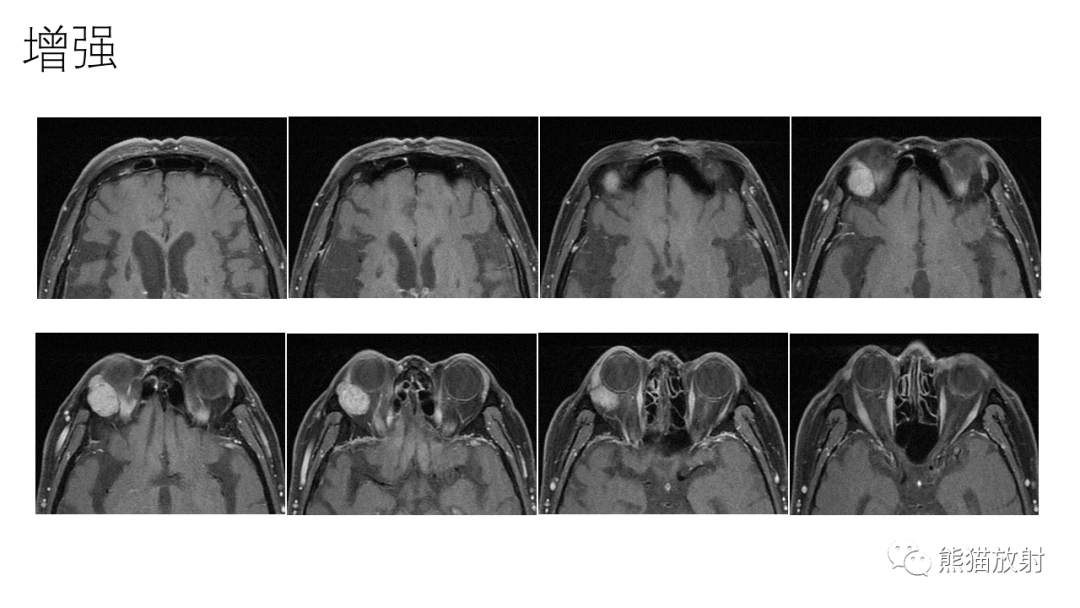

【PPT】泪腺多形性腺瘤 VS 眼眶淋巴瘤-5